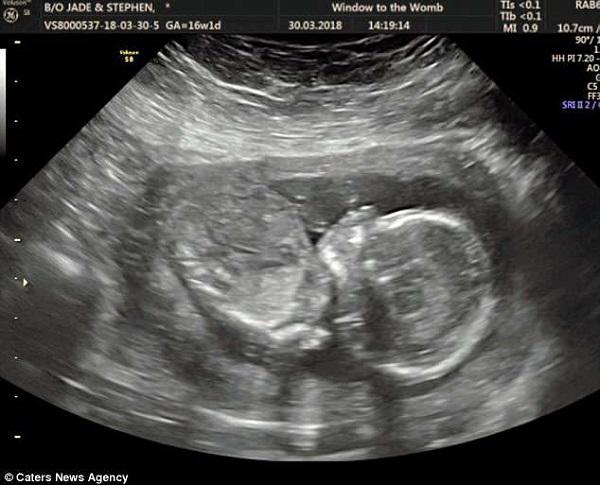

Nói về giới tính đứa con trong bụng của mình, chị Jade cho biết chị đã nghĩ rằng lần này chị mang bầu một bé trai bởi cảm giác và các biểu hiện cũng rất khác so với khi mang thai bé Ruby lần đầu. Vì vậy, khi bác sĩ siêu âm cho biết trong bụng chị là một bé gái, chị đã hơi ngạc nhiên và có ý định siêu âm lại một lần nữa.

Giờ đây, em bé trong bụng chị Jade đã được 19 tuần tuổi và chị dự định sẽ đi khám thai vào tuần tới để xác định chính xác giới tính của con. Bà mẹ trẻ vô cùng háo hức sự ra đời của đứa con thứ 2: “Tôi mong lần khám thai này xác định được chính xác giới tính của em bé, cho dù là bé gái hay bé trai, tôi và gia đình đều cực kỳ mong chờ.”